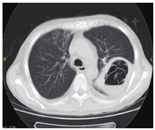

例1 术后早期发生移植物功能恢复延迟(DGF),予以ATG治疗后恢复顺利,出院。术后7个月时因发热、呼吸窘迫入院,入院后予以无创呼吸机辅助呼吸,开始大包围治疗(美罗培南、替考拉宁、伏立康唑、复方新诺明片、更昔洛韦、异烟肼、利福平、乙胺丁醇、吡嗪酰胺等),并加用免疫球蛋白提升免疫力治疗。入院第3周受者出现胸痛、咯血,复查肺部CT,原左肺上叶实变病灶中出现空洞(图1),考虑曲霉空洞,重点予以伏立康唑抗曲霉治疗;复查肺部CT提示空洞较前增大,受者症状继续加重未能缓解,后行经皮肺穿刺活检提示空洞为毛霉菌病,遂予以两性霉素B脂质体(逐日递增至维持剂量1 mg·kg-1·d-1)及氟胞嘧啶(4 g/d),1周后复查肺部CT提示左肺空洞稍有增大,考虑毛霉菌感染未得到控制,将两性霉素B脂质体用量逐渐增大到2 mg·kg-1·d-1(100 mg/d),予以两性霉素B脂质体治疗22 d时复查CT,空洞缩小,此时免疫抑制剂尚未完全恢复,仅口服甲泼尼龙(12 mg/d)。受者回当地医院继续两性霉素B脂质体及氟胞嘧啶治疗至痊愈,整个治疗过程中停用他克莫司70 d,停用MMF121 d后改咪唑立宾,两性霉素B脂质体共使用65 d(100 mg/d治疗35 d后根据复查肺部CT检查及肾功能情况逐渐递减为60 mg/d、20 mg/d至停用),治疗过程中尿量基本正常,血肌酐波动于130~203 mmol/L,治疗结束后45 d复查血肌酐处于正常范围,未发生排斥反应。